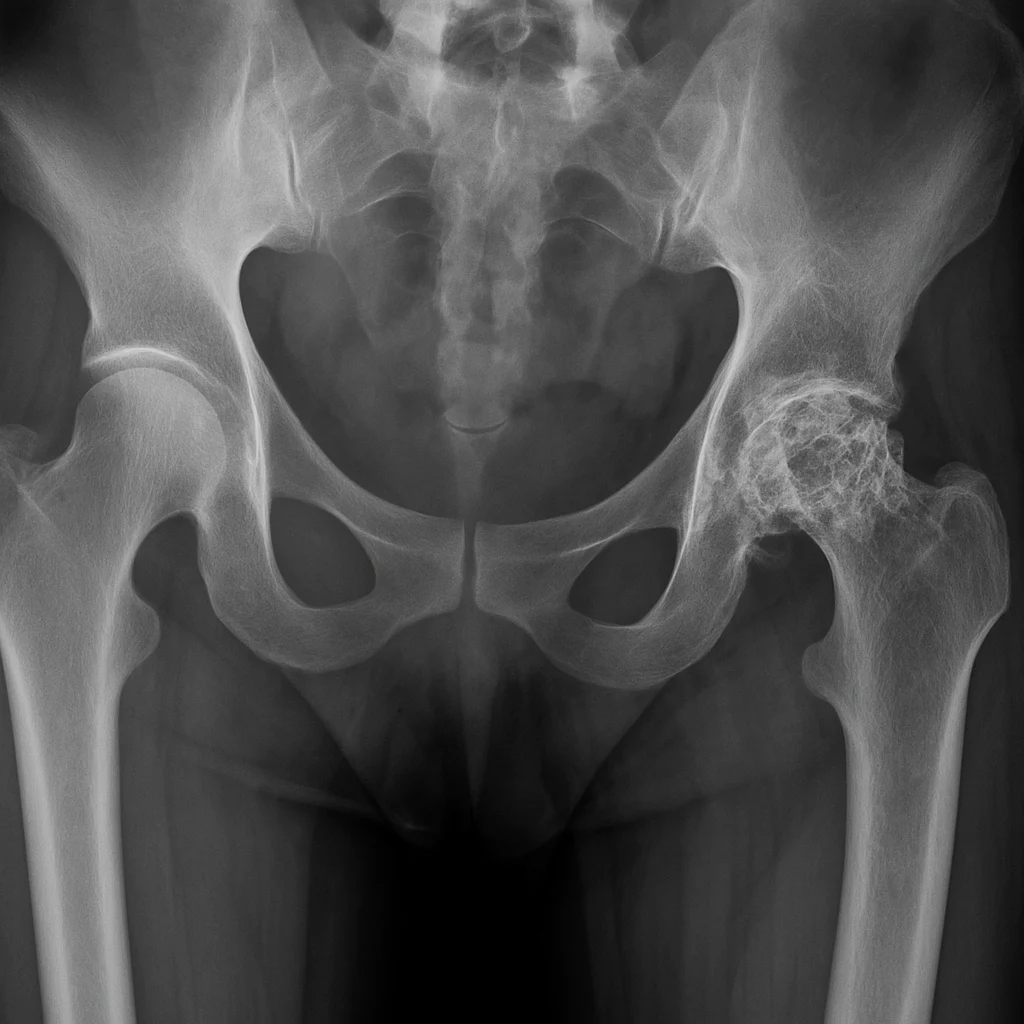

Kalça kireçlenmesi, tıbbi adıyla osteoartrit, kalça eklemindeki kıkırdağın aşınması ve kemiklerin birbirine sürtünmesiyle ortaya çıkan kronik bir eklem hastalığıdır. Ağrı, hareket kısıtlılığı ve yaşam kalitesinde düşüşle sonuçlanır. Erken teşhis edildiğinde, kalça kireçlenmesi tedavisi genellikle ameliyatsız yöntemlerle yönetilebilir. Samsun’da, Doç. Dr. Ömer Bozduman gibi uzmanlar, PRP (trombosit zengin plazma), kök hücre tedavisi, ozon tedavisi ve kalça […]